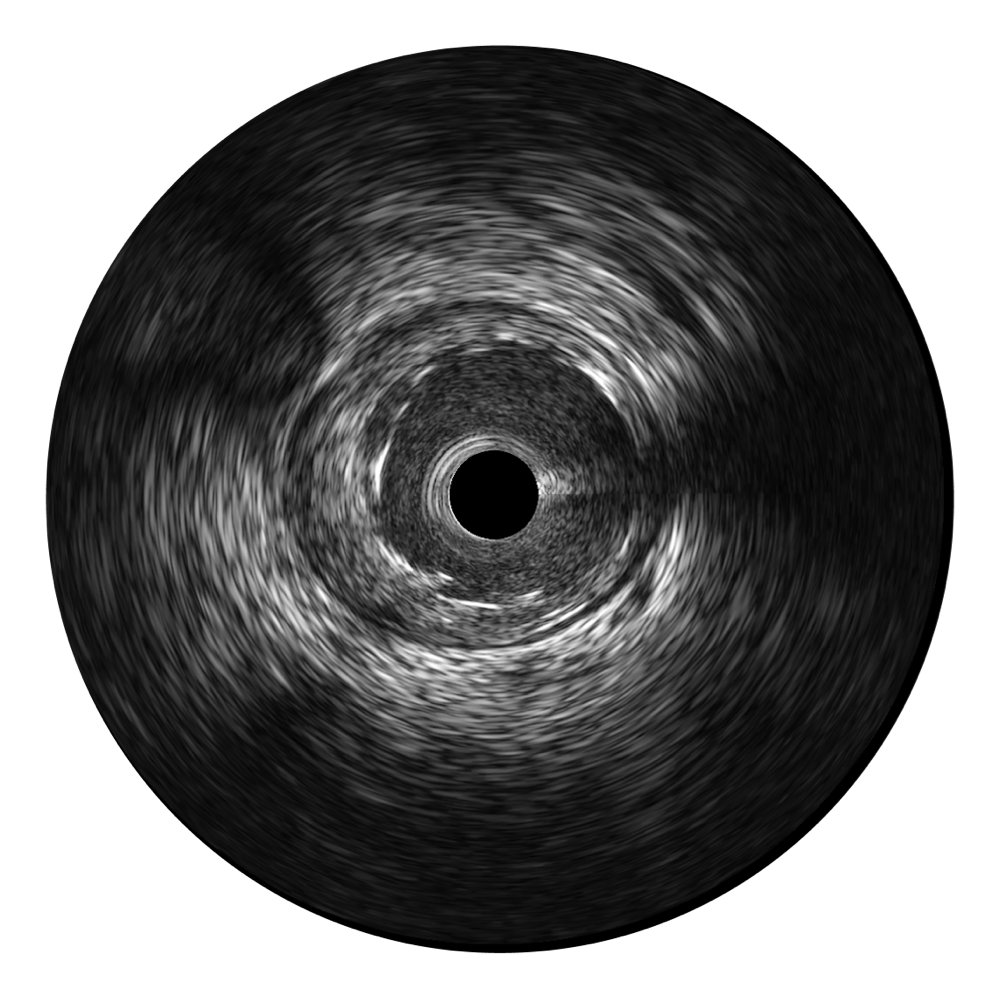

传统IVUS图像

对比传统IVUS导管成像,米兰官方网站宽频IVUS图像的近场支架梁显影更细腻,远场中膜外血管仍清晰可辨,兼顾远中近,兼顾分辨力与穿透深度